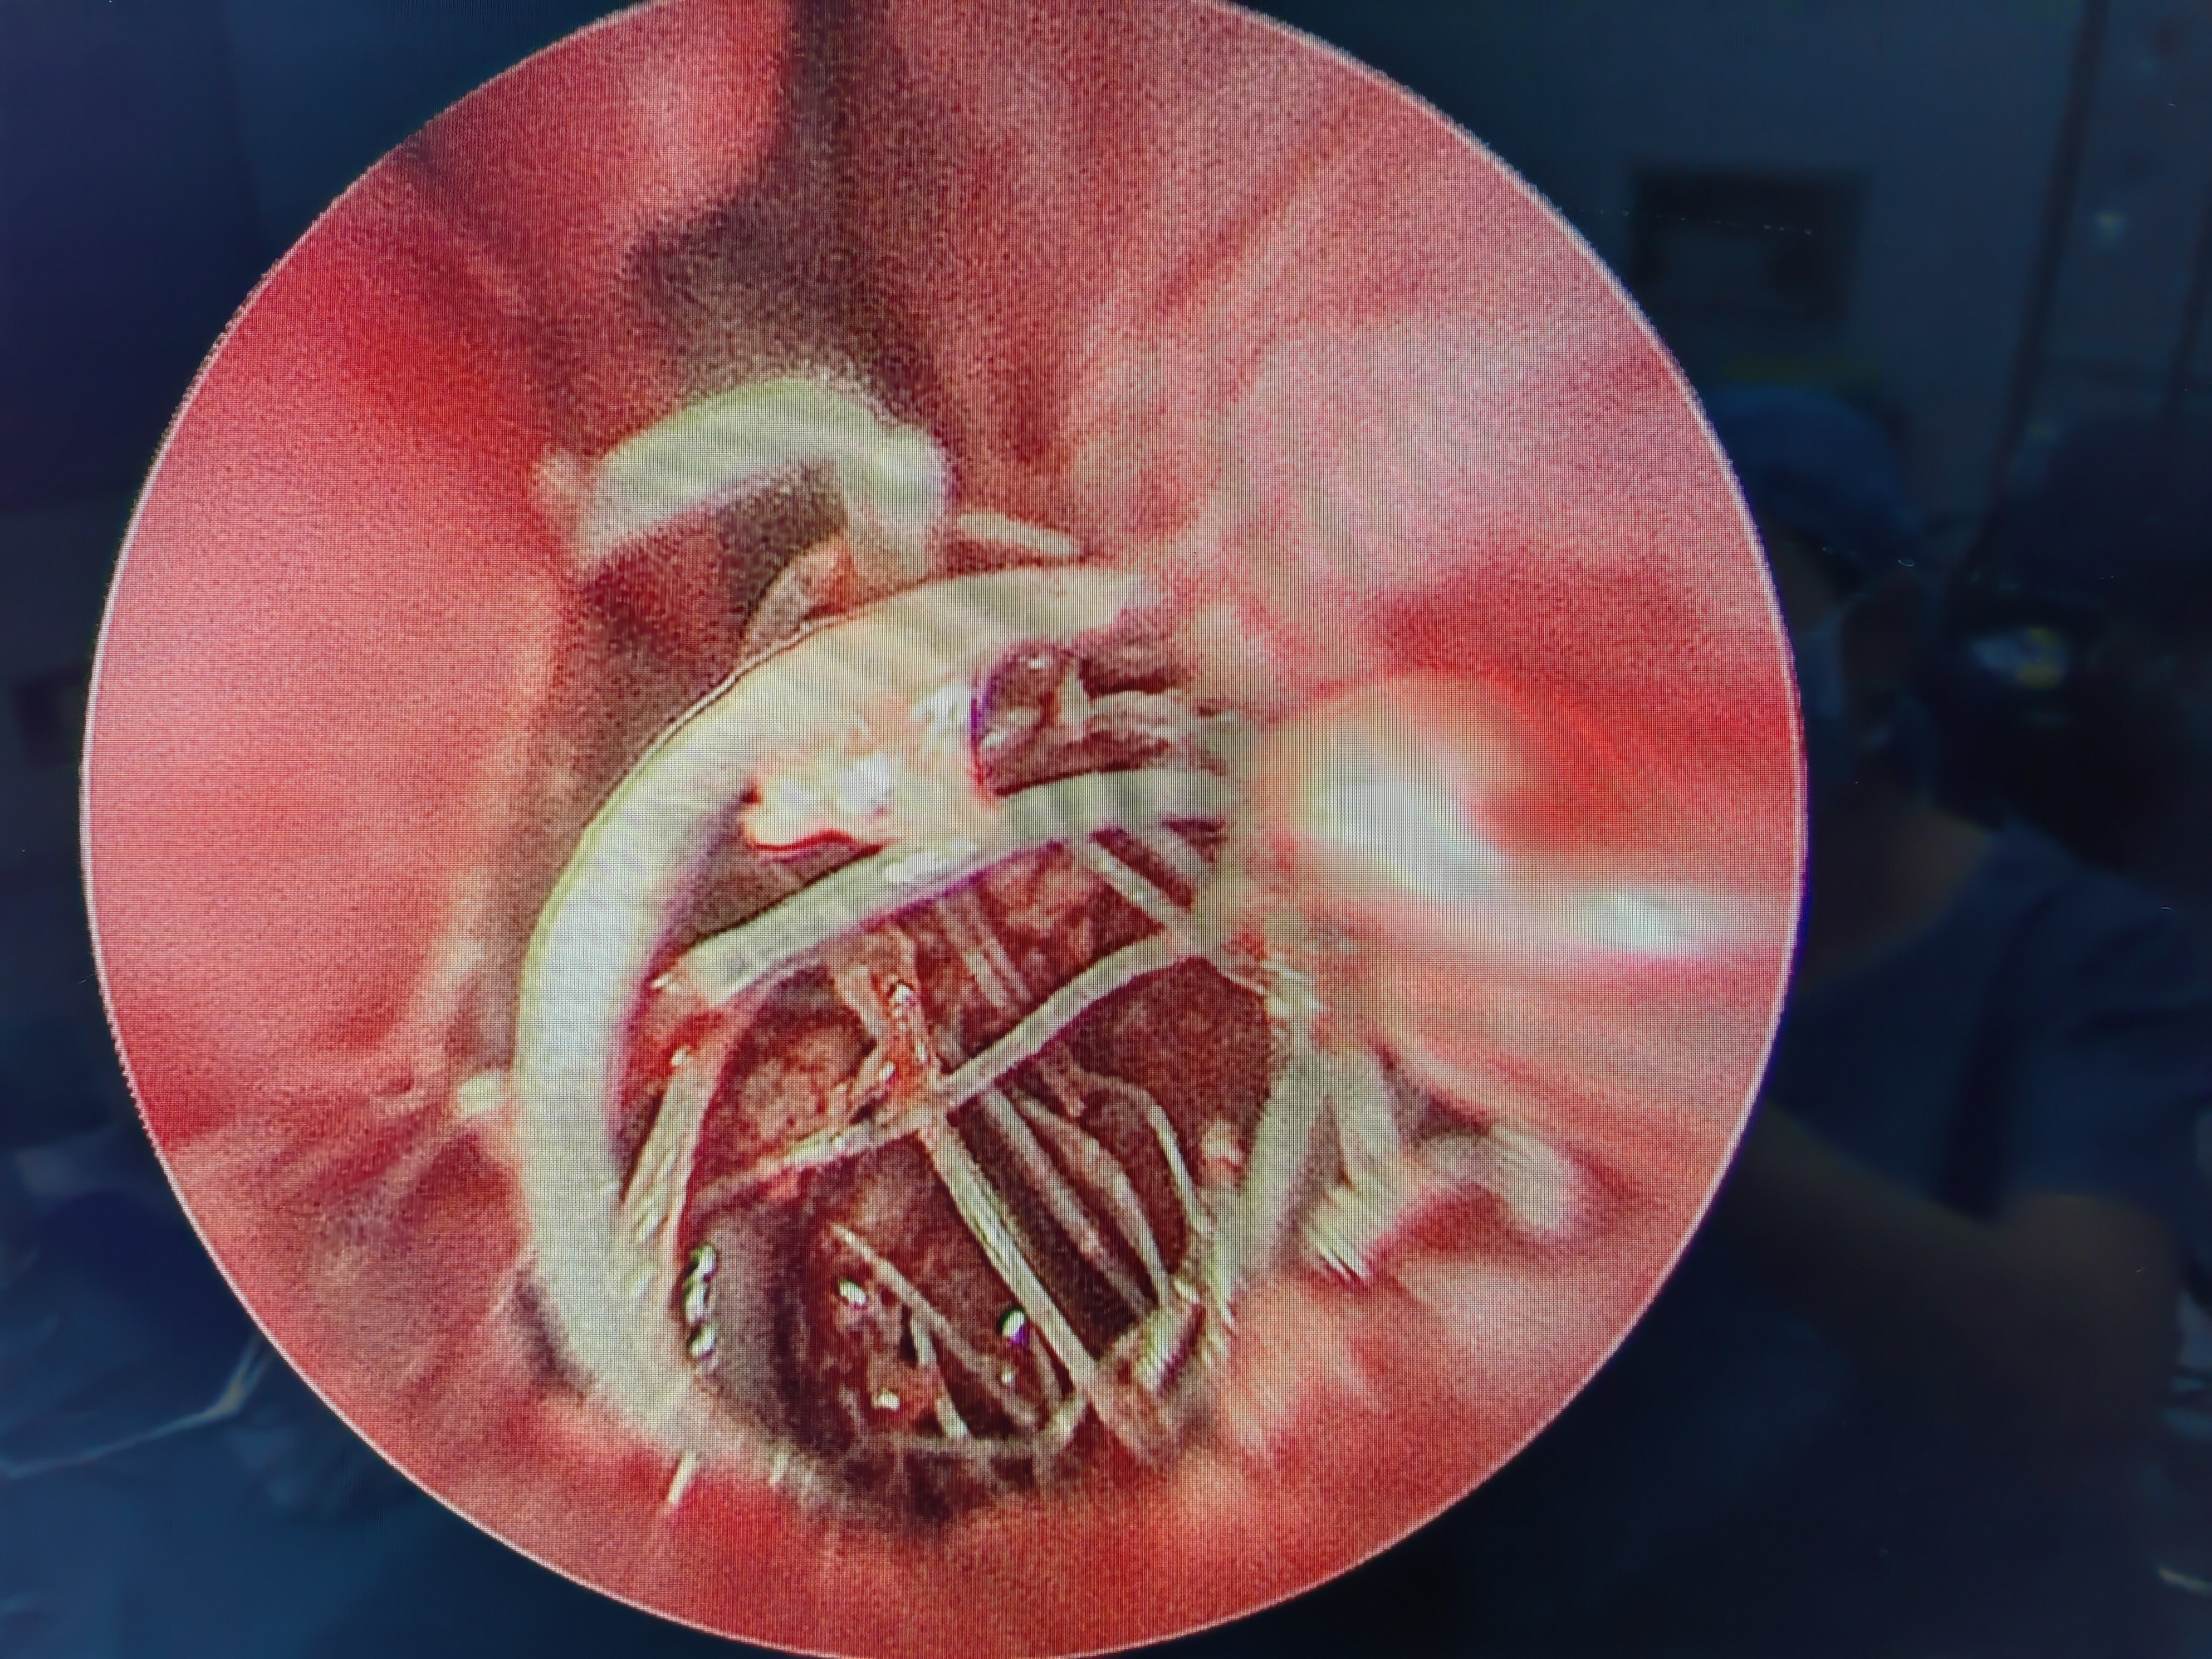

术中放入的可吸收药物支架 预防肉芽和狭窄